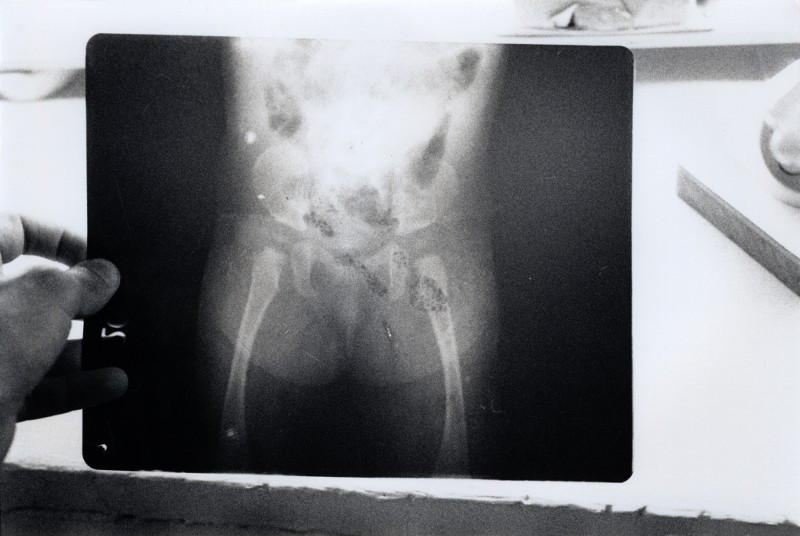

Aujourd'hui prise de vues dans la clinique Sambhavna, entre médecine allopathique, ayurvédique avec leur propre fabrication de pilules, panchakarma (massage à l'huile et vapeur ayurvédique...), yoga, centre de documentation etc... Il y a de quoi faire ! Puis je retourne au Chingari Trust. Ce que j'y verrai restera grave dans ma mémoire: après la classe habituelle, je vais dans la salle de physiothérapie, et une mère finit par amener sa fille de 5 ans mais je suis sur qu'elle est plus petite que ma nièce d'à peine 2 ans. Elle ne bouge pas après qu'elle l'ait posé à terre. Elle semble comme morte, et ses jambes si fines ne contredisent pas cette version, ni sa tête mal tenue, en arrière, et ses yeux a demi-clos. Le regard plein de questions mêlé d'espoir de sa mère en dit long sur la tragédie qu'elle vit au quotidien. Le médecin pense à une paralysie cérébrale ou spinale. Un peu plus tard, en voyant le dossier médical de la petite Apeksha, je tombe sur une radio faite à l'âge de 9 mois qui me sidère: les fémurs n'ont pas de tête, et certainement pas de cartilage de croissance, le bassin est constitue d'un tas d'os non soudés...